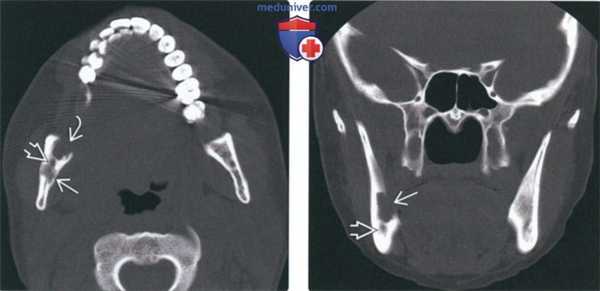

(Слева) На рентгенограмме черепа в прямой проекции визуализируются два очага ЛКГ в лобной кости: меньший (округлый с ровными контурами) и больший (неправильной формы). Для описания подобных поражений используется термин «географический череп». Очаги также определяются в нижней челюсти.

(Справа) На рентгенограмме в косой боковой проекции у этого же пациента определяется «выскобленный» очаг вокруг мезиального корня формирующегося 1-го моляра. Пациент страдает хроническим диссеминированным ЛКГ, клинически проявляющимся экзофтальмом.

2. Рентгенография при лангергансоклеточном гистиоцитозе челюсти:

• Интра- и экстраоральная рентгенография:

о Утрата костной ткани вокруг зуба на всем протяжении

о Может имитировать заболевание периодонта: следующие признаки могут помочь в дифференциальной диагностике:

- Заболевание периодонта начинается с альвеолярного гребня; очаги ЛКГ обычно центрированы возле средней трети корня

- В отличие от заболеваний периодонта кость может выглядеть «выскобленной»

о Зубы могут выглядеть «парящими»

о На панорамных изображениях могут обнаруживаться периостальные наслоения вдоль кортикальной пластинки

• Краниография:

о Позволяет обнаружить поражения черепа:

- «Выштампованные», относительно хорошо отграниченные

- Очаги могут иметь неправильную форму и больший размер, иногда создавая картину «географического черепа»